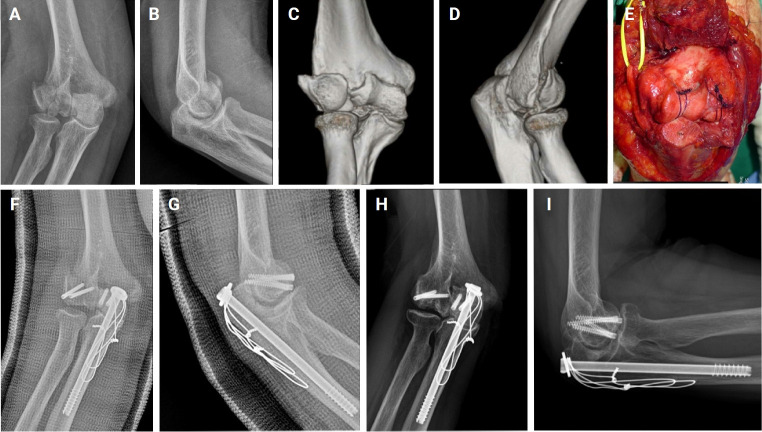

Methods: This study enrolled 21 elbows in DHCS fracture (group A) from 2007 to 2017 and 30 elbows in elbow dislocation (group B) in 2020, all of whom attended a single trauma center. Group A was divided by immobilization period into less than 3 weeks (A1) and more than 3 weeks (A2). Injury patterns of the anterior capsule were divided into proximal stripping, middle displaced, and distal avulsion on magnetic resonance imaging (MRI) scans. Range of motion and functional outcomes were compared between groups A1 and A2.

Results: All patients in group A exhibited proximal stripping of the anterior capsule, while group B showed middle displaced (37%) and distal avulsion (63%) injuries (P<0.001). The mean flexion contracture was 2° in A1 and 8° in A2 (P=0.139), demonstrating no significant difference by immobilization duration. Similarly, the groups had no significant differences in Mayo Elbow Performance Score (MEPS) or Disabilities of the Arm, Shoulder and Hand (DASH) scores.

Conclusions: Flexion contracture following elbow trauma appears to be more closely related to the pattern of anterior capsule injury than the duration of immobilization. Early identification of anterior capsule injury patterns via MRI could inform treatment decisions, particularly in cases where stable surgical fixation is challenging. Prolonged immobilization may be a viable adjuvant treatment option in such cases. Level of evidence: III.